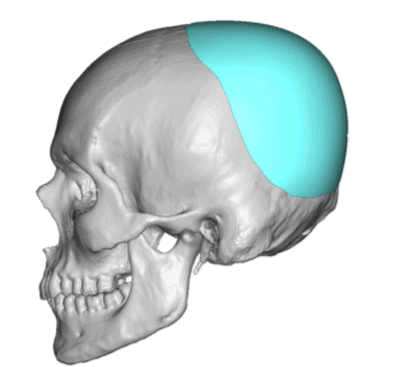

Desire for a higher and more prominent crown of the skull.

Crown of skull augmentation using a custom skull implant.

Desire for a higher and more prominent crown of the skull.

Crown of skull augmentation using a custom skull implant.